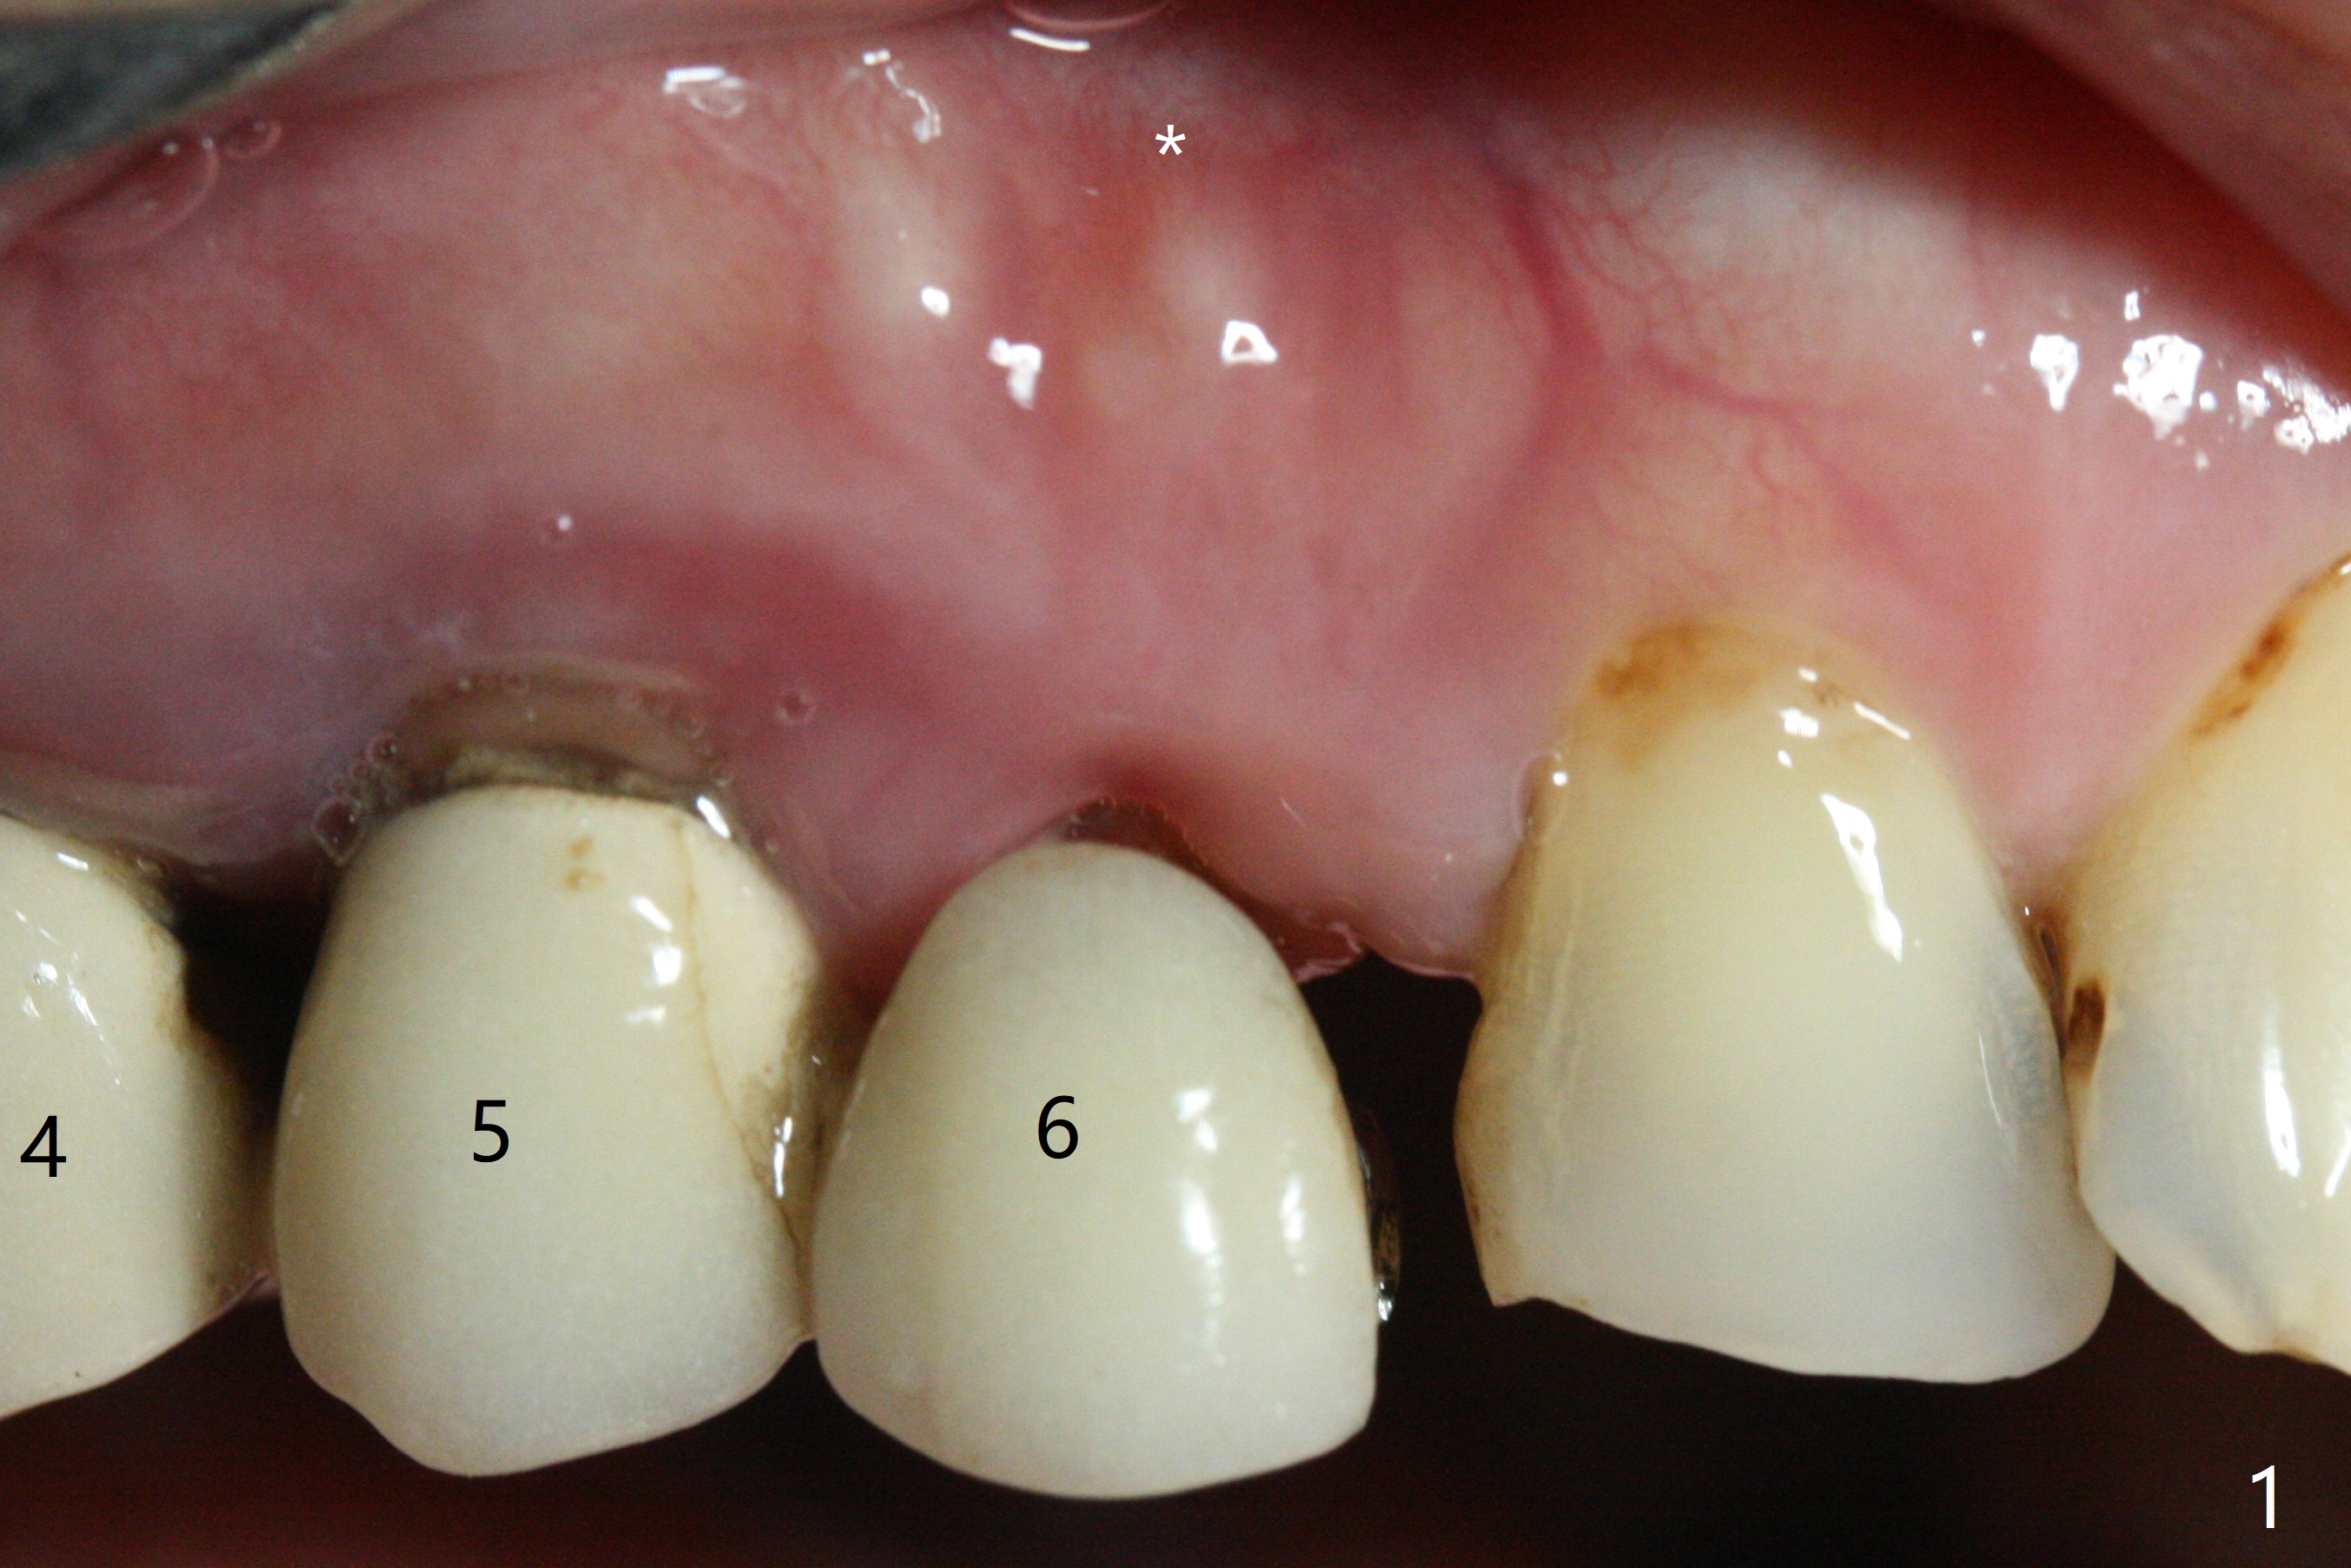

After removal the pontic of a cantilever FPD (Fig.1), a residual root is found at #6 with the buccal concavity (Fig.2 *). The ridge is narrow with flap elevation (Fig.3). PA taken with a 1.2 mm drill for 14 mm shows a horizontally impacted canine (Fig.4: #6). When the osteotomy is finished without apparently buccal perforation (Fig.5), the trajectory is buccal. When a 3x14 mm (12.5 mm in bone) 15 degree angled 1-piece implant is placed with normal trajectory (Fig.6), the buccal plate is perforated. As the implant is redirected so that the apical end of the implant does not stick out buccally, the trajectory returns buccal (Fig.7). The buccal aspect of the abutment is heavily reduced for an immediate provisional. The perforation is repaired with Vanilla Graft and Collagen Dressing before suturing. CT should have been taken preoperatively; the osteotomy should have been initiated as palatal as possible, as compared to that in Fig.5. When the 1st drill is used. it should be checked for restoration. An angled abutment does not help the trajectory substantially. The implant is loose 1.5 months (partially due to mastication); after retightening, CT is taken (Fig.8). The implant is within the bone. If the implant becomes loose again, extract the impacted canine and place the longest implant (22 mm) palatally. The implant is stable nearly 4.5 months postop (Fig.9). The patient is not satisfied with buccally-placed crown. The implant is removed with bone graft 6 months postop.